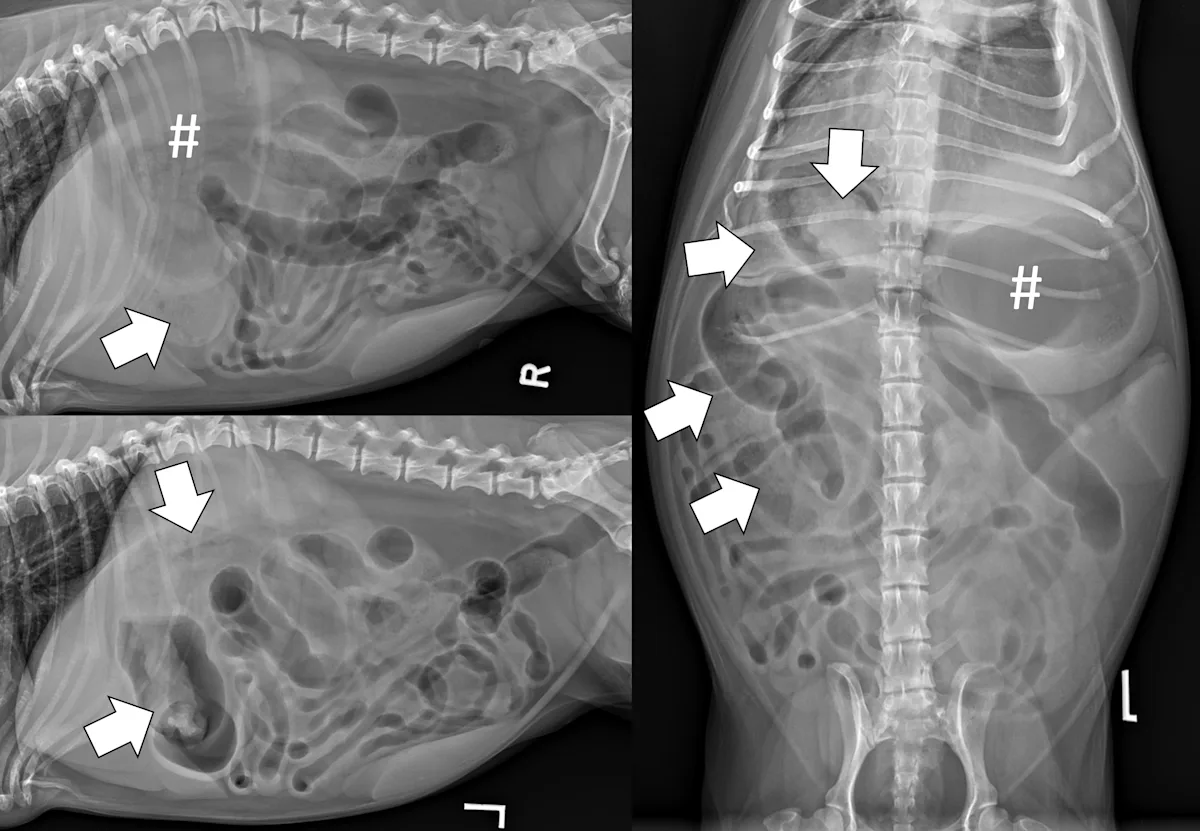

Evaluate the peritoneal space for decreased serosal detail and/or free gas, the combination of which strongly suggests septic peritonitis secondary to GI perforation (Figure 2).

Right lateral and ventrodorsal abdominal radiographs of a 10-month-old neutered male pit bull with a small intestinal mechanical obstruction of undetermined etiology. The stomach is moderately dilated with fluid and gas (pound signs), and there is moderate segmental dilation of the small bowel with stacking and hairpin turns (asterisks). Peritoneal serosal detail is diffusely decreased with a small, tear-drop–shaped intraperitoneal gas bubble between the liver and stomach (arrow) consistent with septic peritonitis secondary to presumed GI perforation.